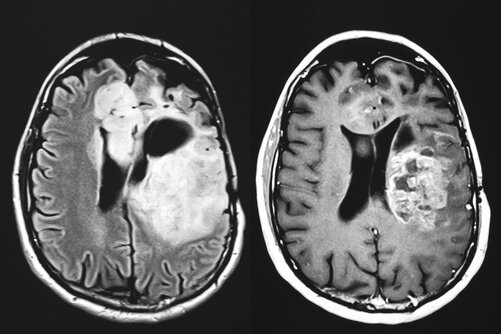

Bildgebung